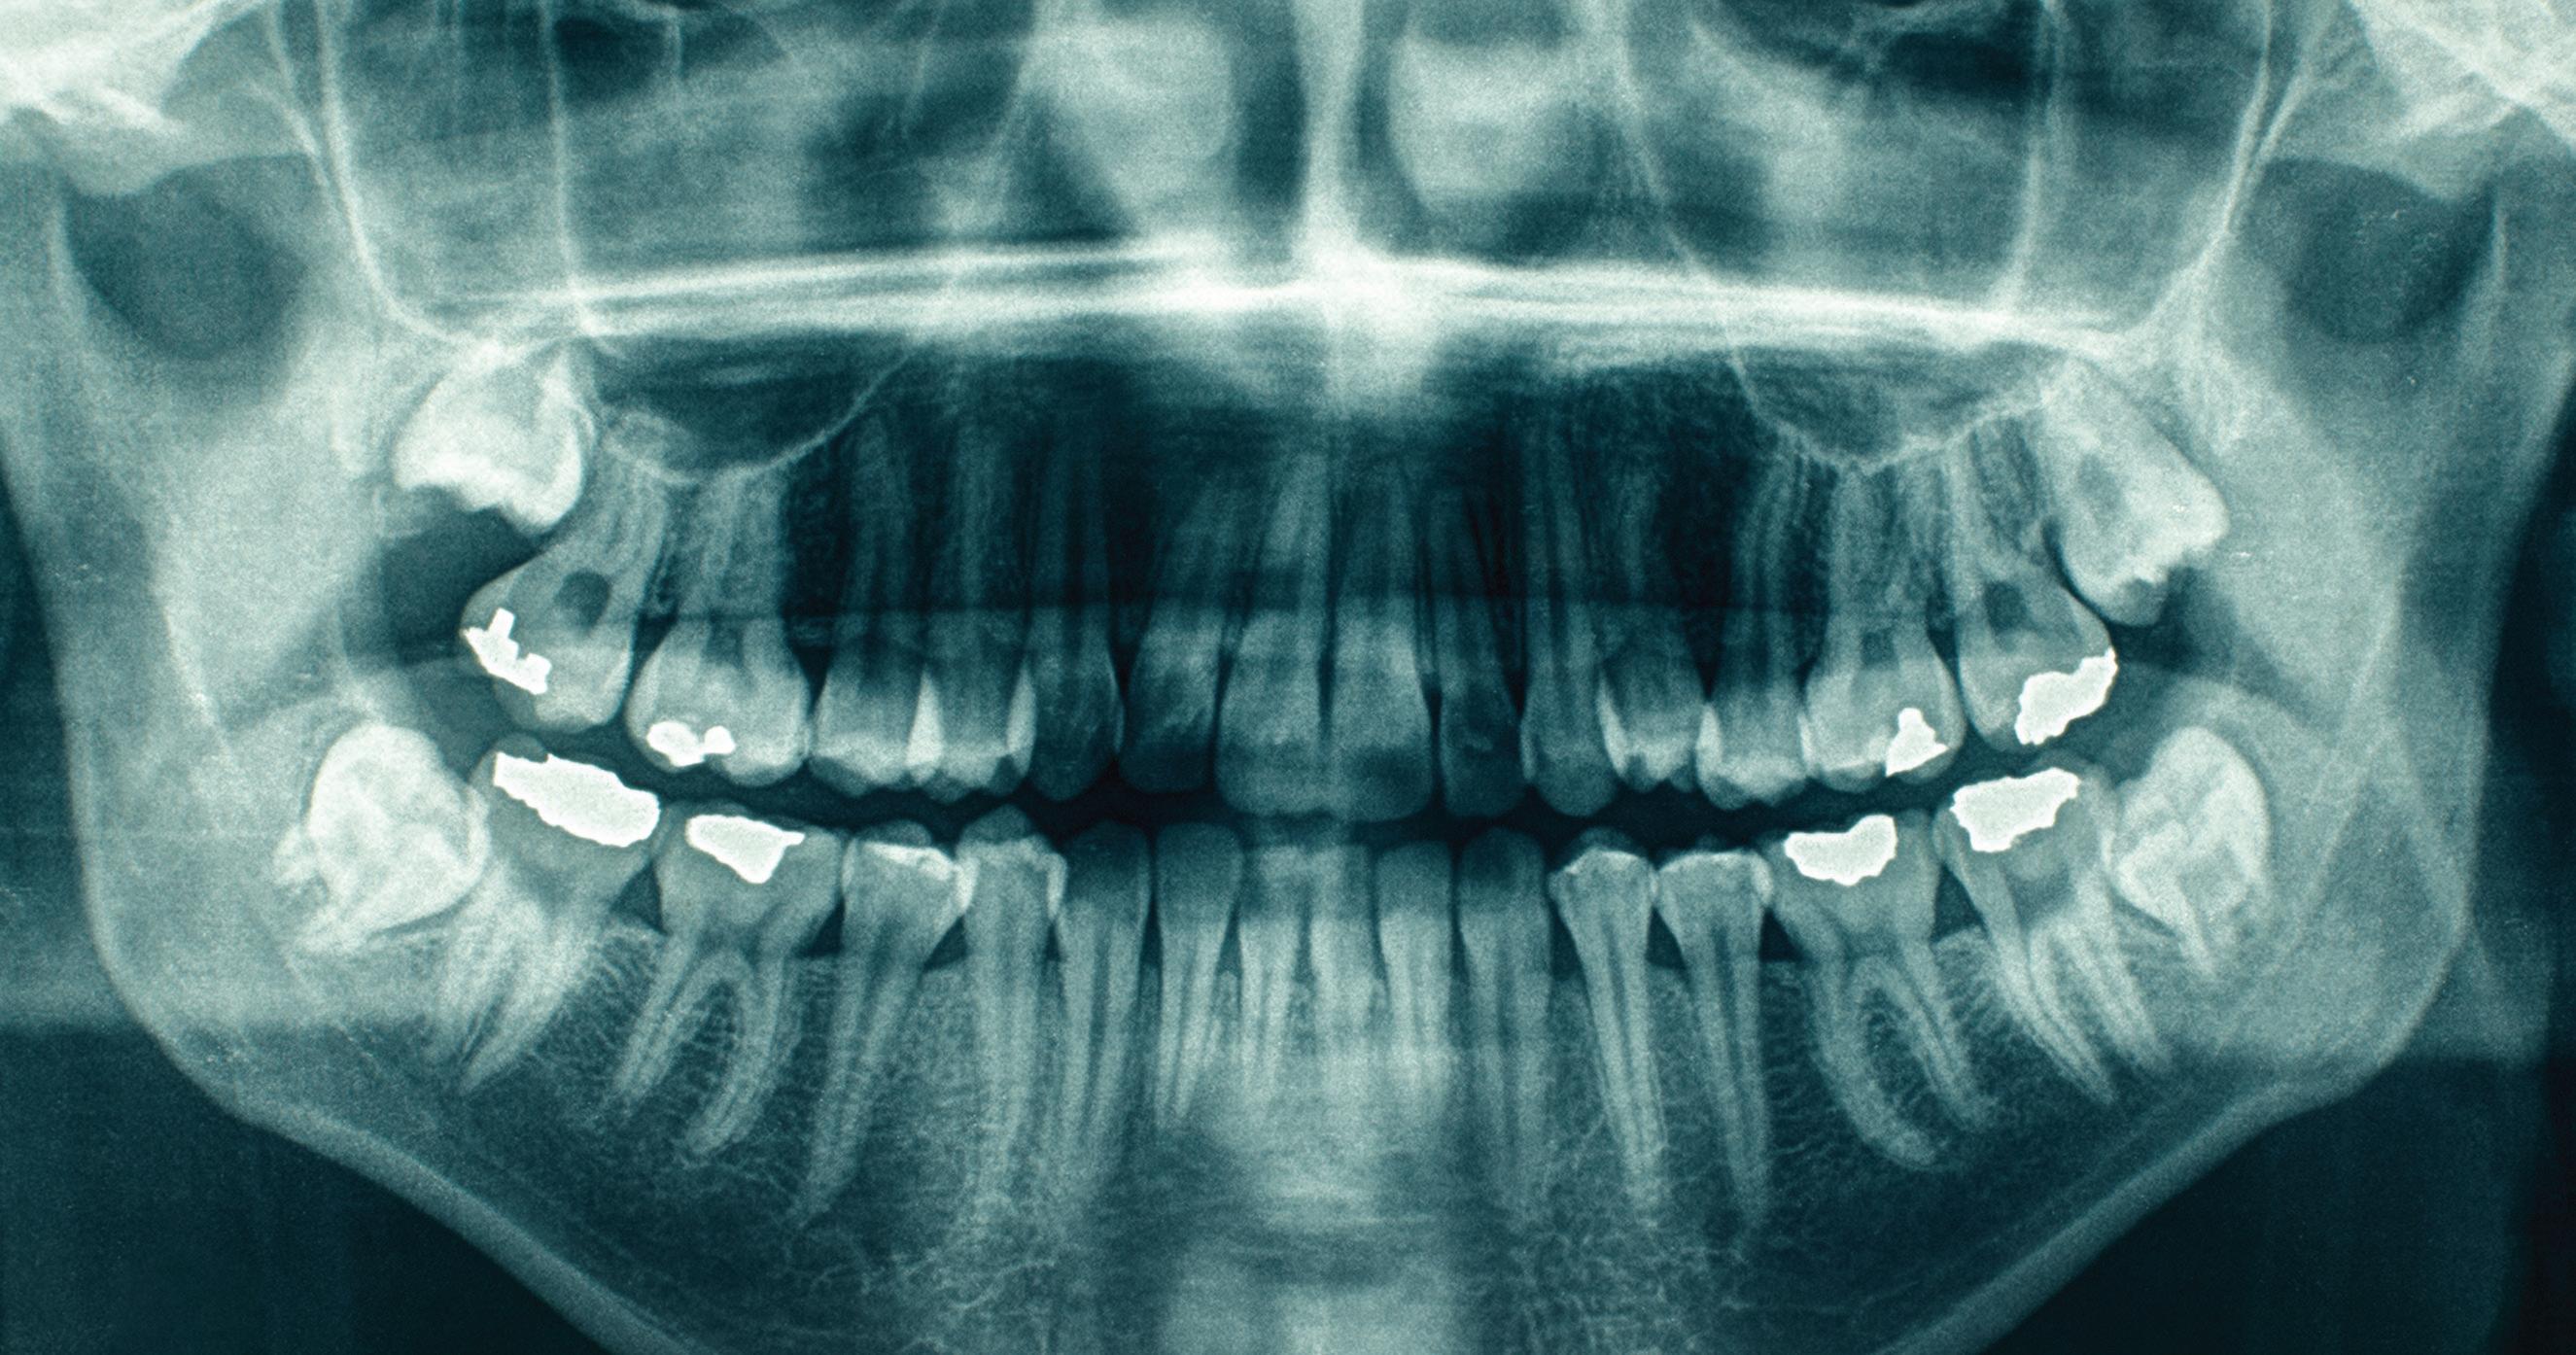

Dental comparison is useful in all these cases, but it depends on our ability to trace dental records back to one or more dental practices. It also depends on the quality of the dental records including (importantly) any images that are available, including 3D scans. We also must assume that the dental records are correctly named. There have been instances in the public dental system of different individuals using the same health care card to secure free appointments. But most importantly, the dental records must still be in existence.

So, this article is a plea. If you’re planning on destroying records, please think about other options such as retaining any electronic record files you have, or scanning your physical documents into electronic files. Physical records certainly take up storage space, but physical x-rays less so. Please try and keep them even if you wish to destroy the written records. Also, some dentists are now investing in 3D scanners so they can retain electronic copies of study models instead of physical copies, which again saves storage space. If you have not yet moved to electronic record storage, at a minimum, we ask that you consider at least retaining physical x-ray or photographic images as they would be extremely helpful for identification of persons who are long since deceased. Images are much more useful to us than written documents.